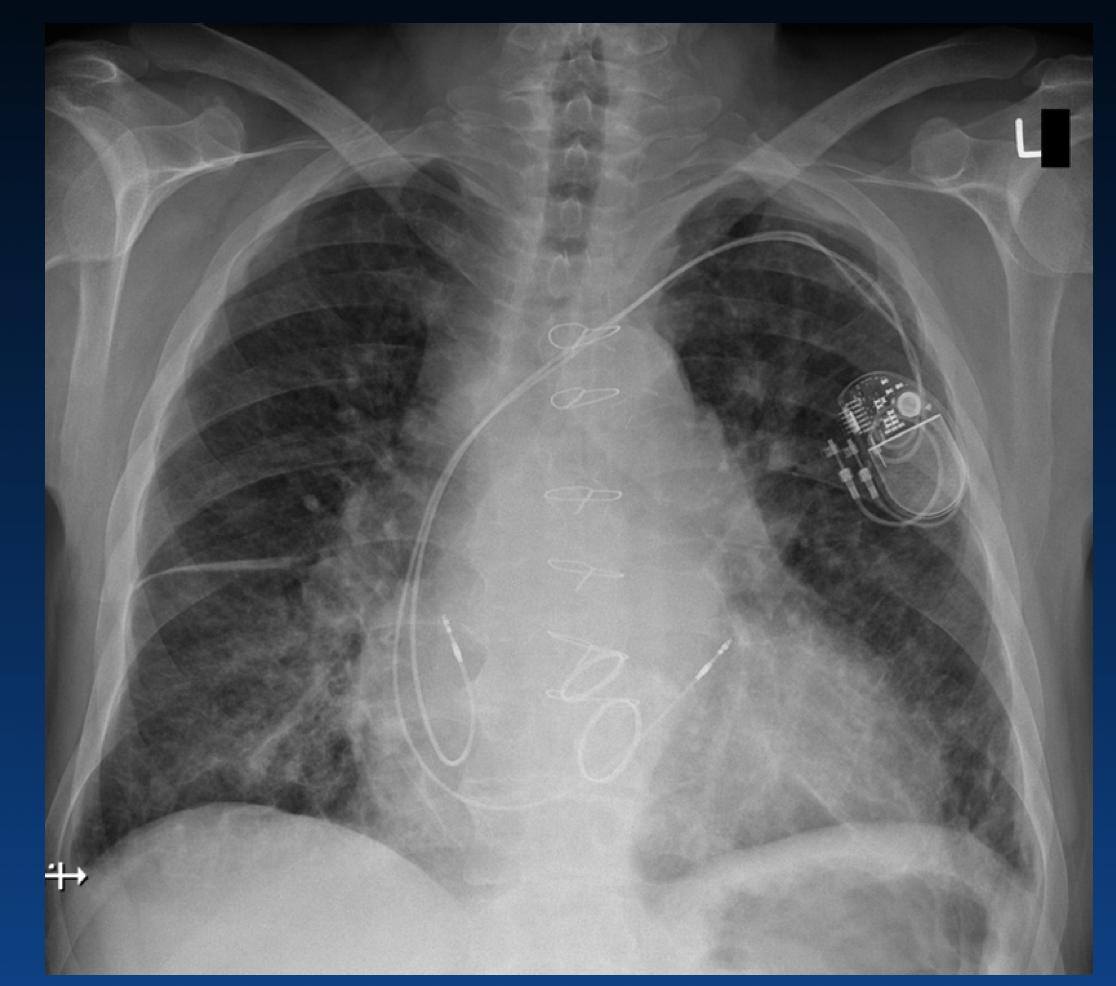

What is shown here?

What kind of pacemaker is described?

What kind of pacemaker is this?

Single Lead Ventricular Pacemaker VVI